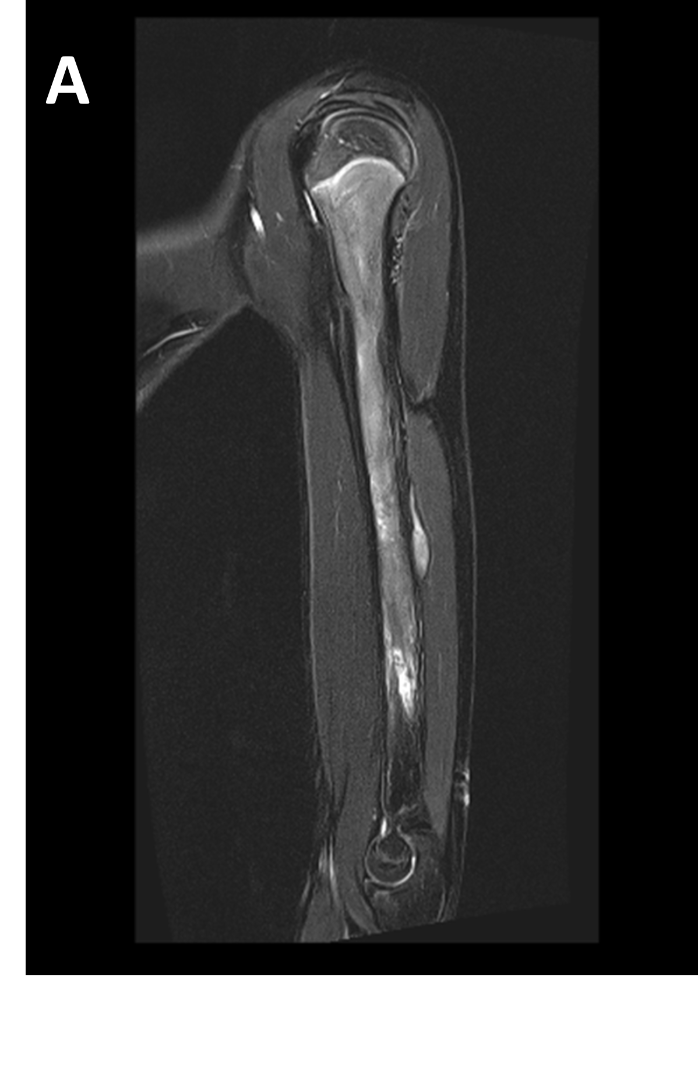

- (A,B) : MR LEFT FOREARM

- A : MR LEFT FOREARM : Fusiform thickening of radial nerve in the posterior compartments of mid-distal 1/3rd arm, as its winds around the spiral groove of the humerus, before piercing the lateral intermuscular septum.